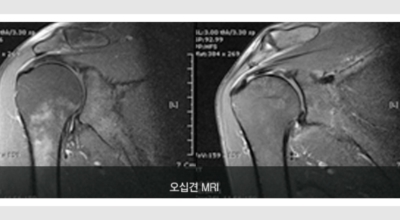

오십견이란?

만성 어깨관절의 통증과 운동제한을 유발하는 가장 흔한 질환의 하나로 전체 인구의 약 2%에서 유발돼요. 동결견이라 하며 흔하게 50세 이후 특별한 원인 없이 심한 통증과 더불어 전 방향으로 능동적, 수동적 관절 운동 범위의 제한을 관찰되는 것이 특징이지요. 꼭 50대에만 발생되는 것이 아니며, 젊은 연령대나 50대 이후에도 발생할 수 있어요.

주로 노화 또는 운동 부족이 오십견의 원인이 돼요. 노화에 따라 어깨 관절 주위의 연부조직이 퇴행성으로 변화해서 오십견이 생깁니다. 이외의 어깨관절의 부상이나 입원 등으로 인해 장기간 어깨관절을 사용하지 못한 경우에도 발생할 수 있어요.